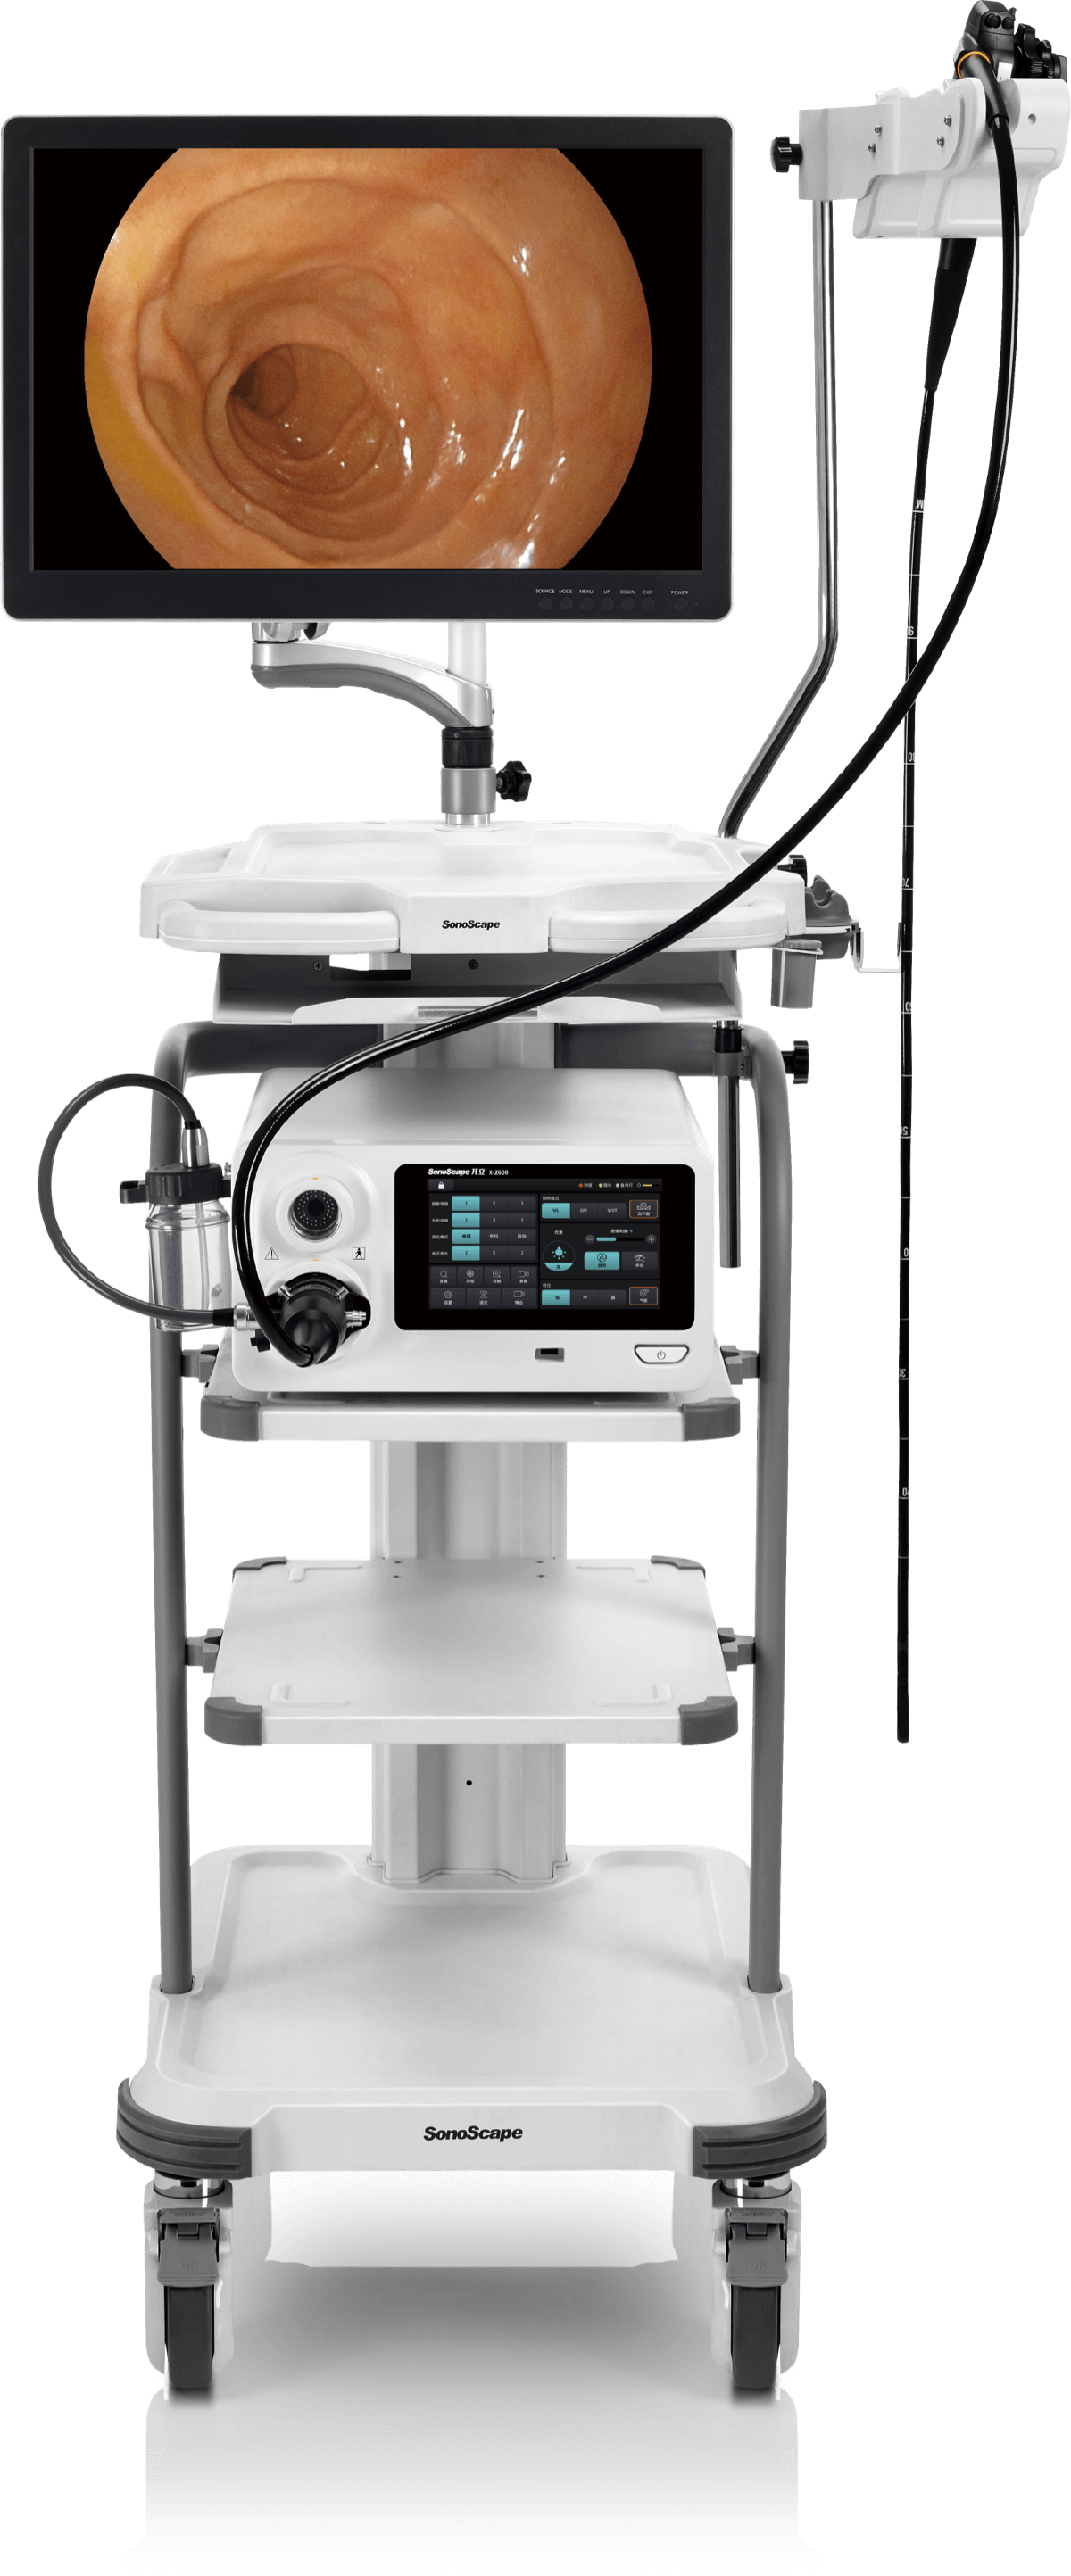

X-2600 系列

高清电子内镜系统

高清电子内镜系统

X-2600系列产品为消化呼吸内镜以及硬镜、外科软镜均支持使用的兼容性平台。医生能够根据手术需要快速切换内镜产品,更好地满足临床需求。

具有聚谱成像技术(SFI)及光电复合染色成像技术(VIST),可完美呈现粘膜细节及病变特征。

1080P视频信号输出,图像清晰。

主机前面板为触摸屏,用户可以轻松调节各种参数,选择所需的功能,极大地提高了使用的便利性。